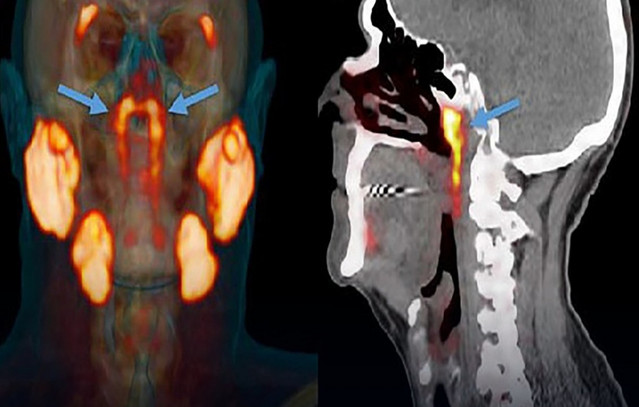

Το πώς βρέθηκαν είναι εξίσου εντυπωσιακό: κατά τη διάρκεια εξετάσεων με αξονικές και PET τομογραφίες σε ασθενείς που είχαν λάβει ενέσεις με ραδιενεργή γλυκόζη, οι ερευνητές παρατήρησαν δύο σημεία στο κεφάλι να «φωτίζονται» αναπάντεχα. Έπειτα από περαιτέρω ανάλυση, κατέληξαν ότι επρόκειτο για άγνωστους μέχρι τότε σιελογόνους αδένες.

Πρόκειται για ένα ζεύγος σιελογόνων αδένων, οι οποίοι είχαν παραμείνει «κρυφοί» για αιώνες. Οι επιστήμονες τούς έδωσαν το όνομα tubarial salivary glands (σωληναριακοί σιελογόνοι αδένες). Ο ρόλος τους είναι να λιπαίνουν και να υγραίνουν την περιοχή του λαιμού πίσω από τη μύτη και το στόμα, εξυπηρετώντας μια ζωτικής σημασίας λειτουργία.